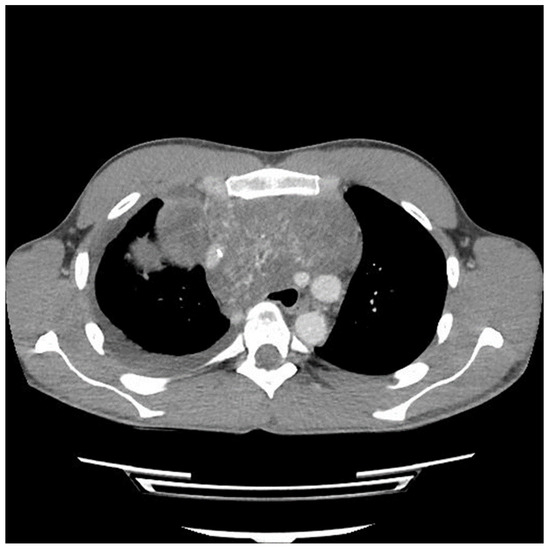

Etoposide, ifosfamide and cisplatin (VIP) chemotherapy was initiated. Bleomycin was not used to avoid pulmonary toxicity, anticipating surgical resection. After the first and second VIP cycles, AFP levels decreased to 1326.96 ng/mL and 219.57 ng/mL, respectively. However, a scheduled computed tomography (CT) scan showed an enlargement of the mass (Figure 2).

Figure 2.

Computed tomography (CT) scan image of mediastinal mass after two cycles of chemotherapy showing interval growth of tumor despite a biochemical response.

A sternotomy was performed using an oscillating saw. A plane was developed between the pericardial fat and pericardium at the level of the inferior vena cava and carried towards the left side of the tumor. Entering the left pleural space allowed release of the tumor from its left lateral attachments and identification of the left phrenic nerve. Fortunately, despite the preoperative CT (Figure 2 and Figure 3) suggesting encasement of the left subclavian artery, distracting the tumor to the right revealed it could be unwrapped and peeled off this vessel, allowing perseveration of it.

The preoperative CT (Figure 1, Figure 2 and Figure 3) identified the involvement of three critical structures: (1) left subclavian artery, (2) right hilum of the lung and (3) SVC. Interestingly, only the encasement of the SVC was confirmed at the time of the surgery. The tumor enveloped the left subclavian on either side but could be peeled off, allowing preservation of the vessel. The tumor abutted the right hilum of the lung but maintained a potential space, so the lesion could simply be lifted off this region. The mass was densely adherent to the lung parenchyma, which was released with cautery. This resulted in a postoperative air leak, which was resolved with conservative management. The encasement of the SVC was the greatest operative challenge. Because the tumor significantly distorted the anatomy of the heart, the SVC was misidentified at the time of surgery, both by direct inspection and TEE evaluation. In retrospect, the use of adjunct techniques, such as a bubble study or the introduction of a wire under direct visualization, could have been helpful in ascertaining the structure intraoperatively. Transaction would have still been required for en bloc resection, but immediate reconstruction of the vessel would have then been possible.